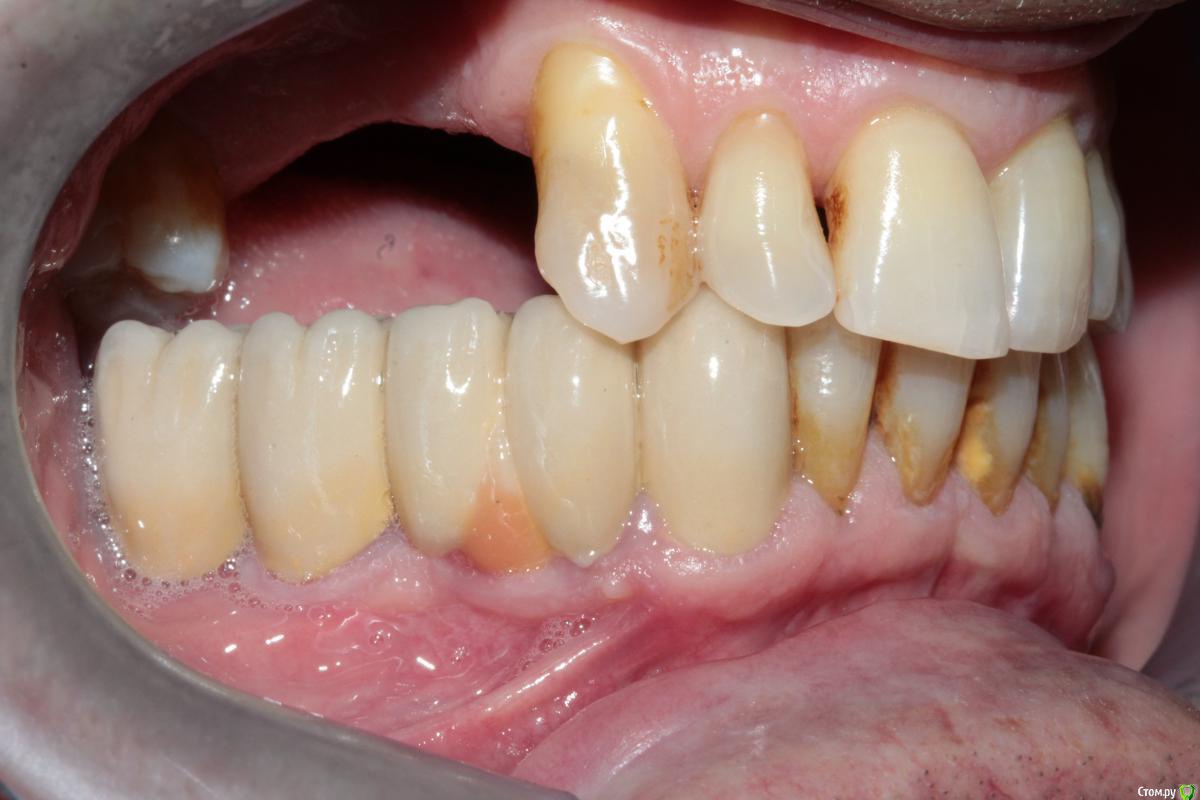

Меня больше смущает 2 момента, 1й - это то что на верхней челюсти зубы "разбросаны" как попало, не знаю что можно сделать не собрав их вместе предварительно. 2ой - в 4ом сегменте мост, консольный, его снимать не хочется, так как его по сути недавно поставили, а не сняв его не знаю что можно сделать в 3ем сегменте, если имплантацию откидываем как вариант....

P.S. - не совсем понятно как получилось  так, что фронт в контакте а премоляры вне контакта (слева).

спасибо за ответ. Я с вами полностью согласен, хороший план, но меня вот беспокоят два момента: 1й - на верхнюю челюсть если сделать бюгель с кламмерами, то в области 24,25 там маленький зазор, а между 25 и 27 там зазор такой, что зуб вроде бы не поместится, в таких случаях там зуб не ставить? просто каркас?

2й момент - слева премоляры вне контакта, если работать под существующий прикус (скорее всего так и будем работать) то они опять останутся без контакта, это не будет проблемой?